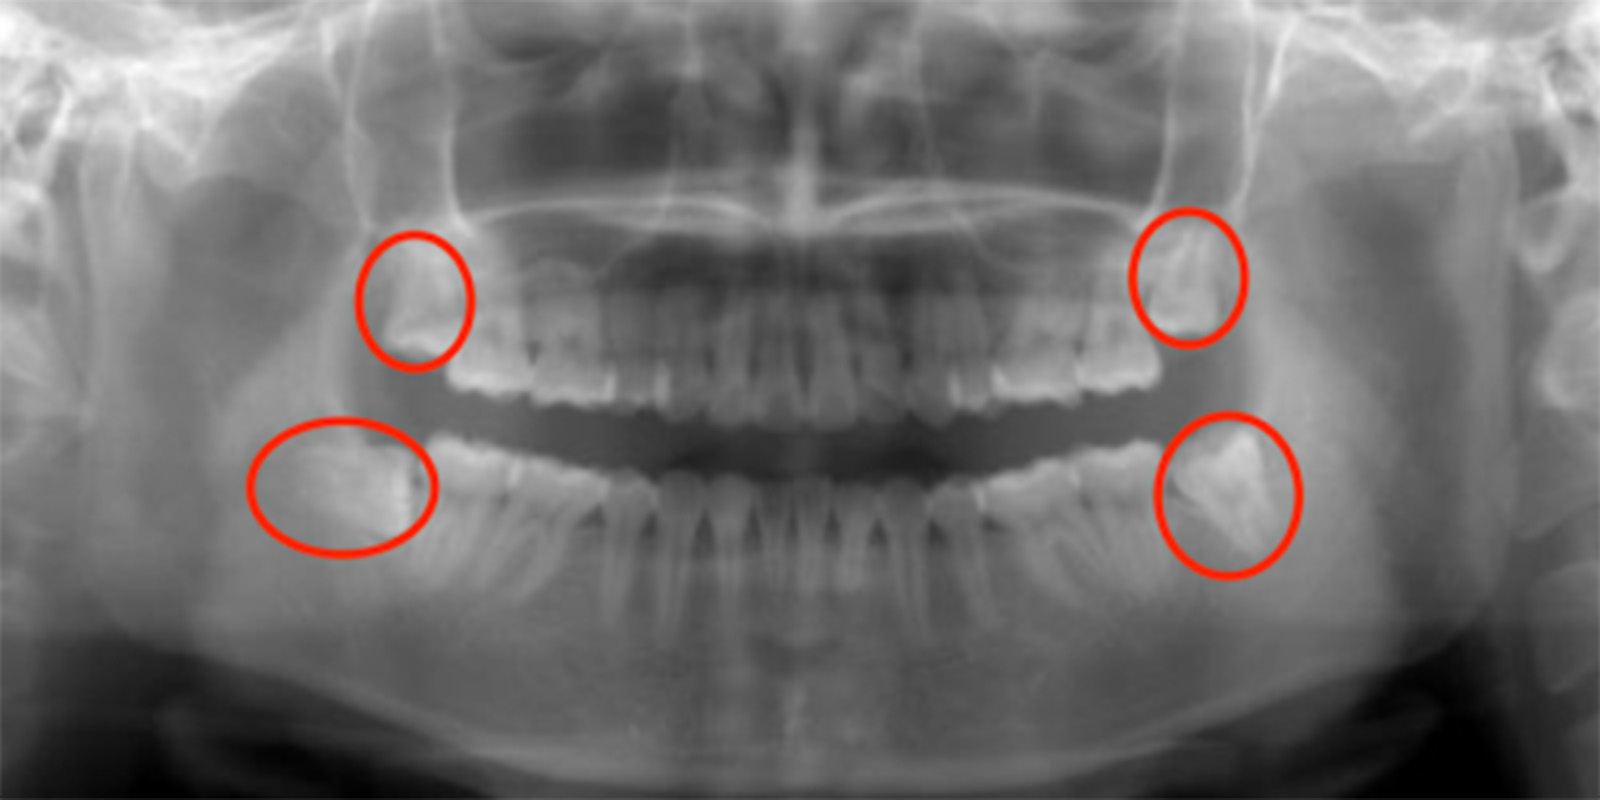

レントゲン画像の親知らず

親知らずがあるレントゲン画像

基本的には、どのようなケースでも

対応します

ただ根の先に下顎管が触れているようなケースであれば2回で対応したりしますが歯の頭の部分が下顎管と触れているような稀なケース、親知らず周りが嚢胞になってしまっているケース、全身疾患がある方、外科処置が困難な方に関しては大学病院を紹介させていただくこともあります。